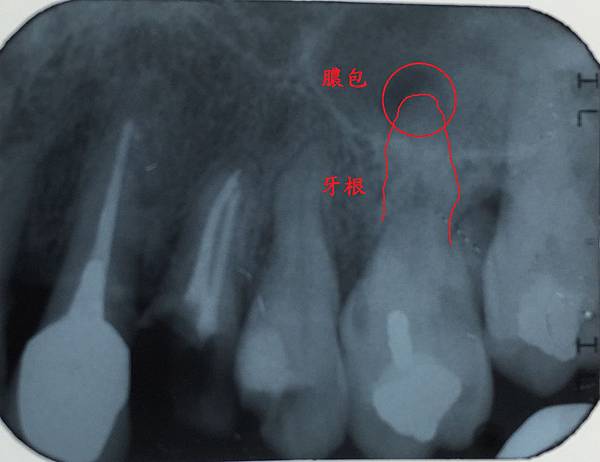

在X光上面是這樣的

X光一般病友不容易看懂

高雄欣美欣樂牙醫標示一下

只要在X光片或口腔內看到根管化膿

大概就知道這顆牙齒很難一次根管治療完成

通常要分兩到三次做

1. 第一次完成神經管清創 擴大 根管開口不封讓膿排出

2. 第二次放藥到膿包的位置 根管開口封閉

3. 第三次觀察症狀理想 完成根管封填

這顆牙齒我們一樣治療到根尖化膿的位置

牙齒內的狀況只能從X光來確認